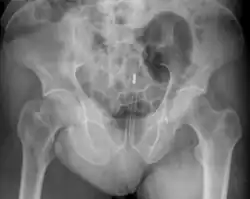

Обычно делают несколько рентгеновских снимков, чтобы точно определить место нахождения инородного тела. Инородные тела из малоконтрастного материала (например, пластика) могут потребовать ультразвукового исследования или компьютерной томографии.[28] Магнитно-резонансная томография противопоказана, особенно если неизвестен материал инородного тела. Инородные тела прямой кишки могут проникать глубоко в толстую кишку, при определённых обстоятельствах вплоть до правого изгиба ободочной кишки.[9]